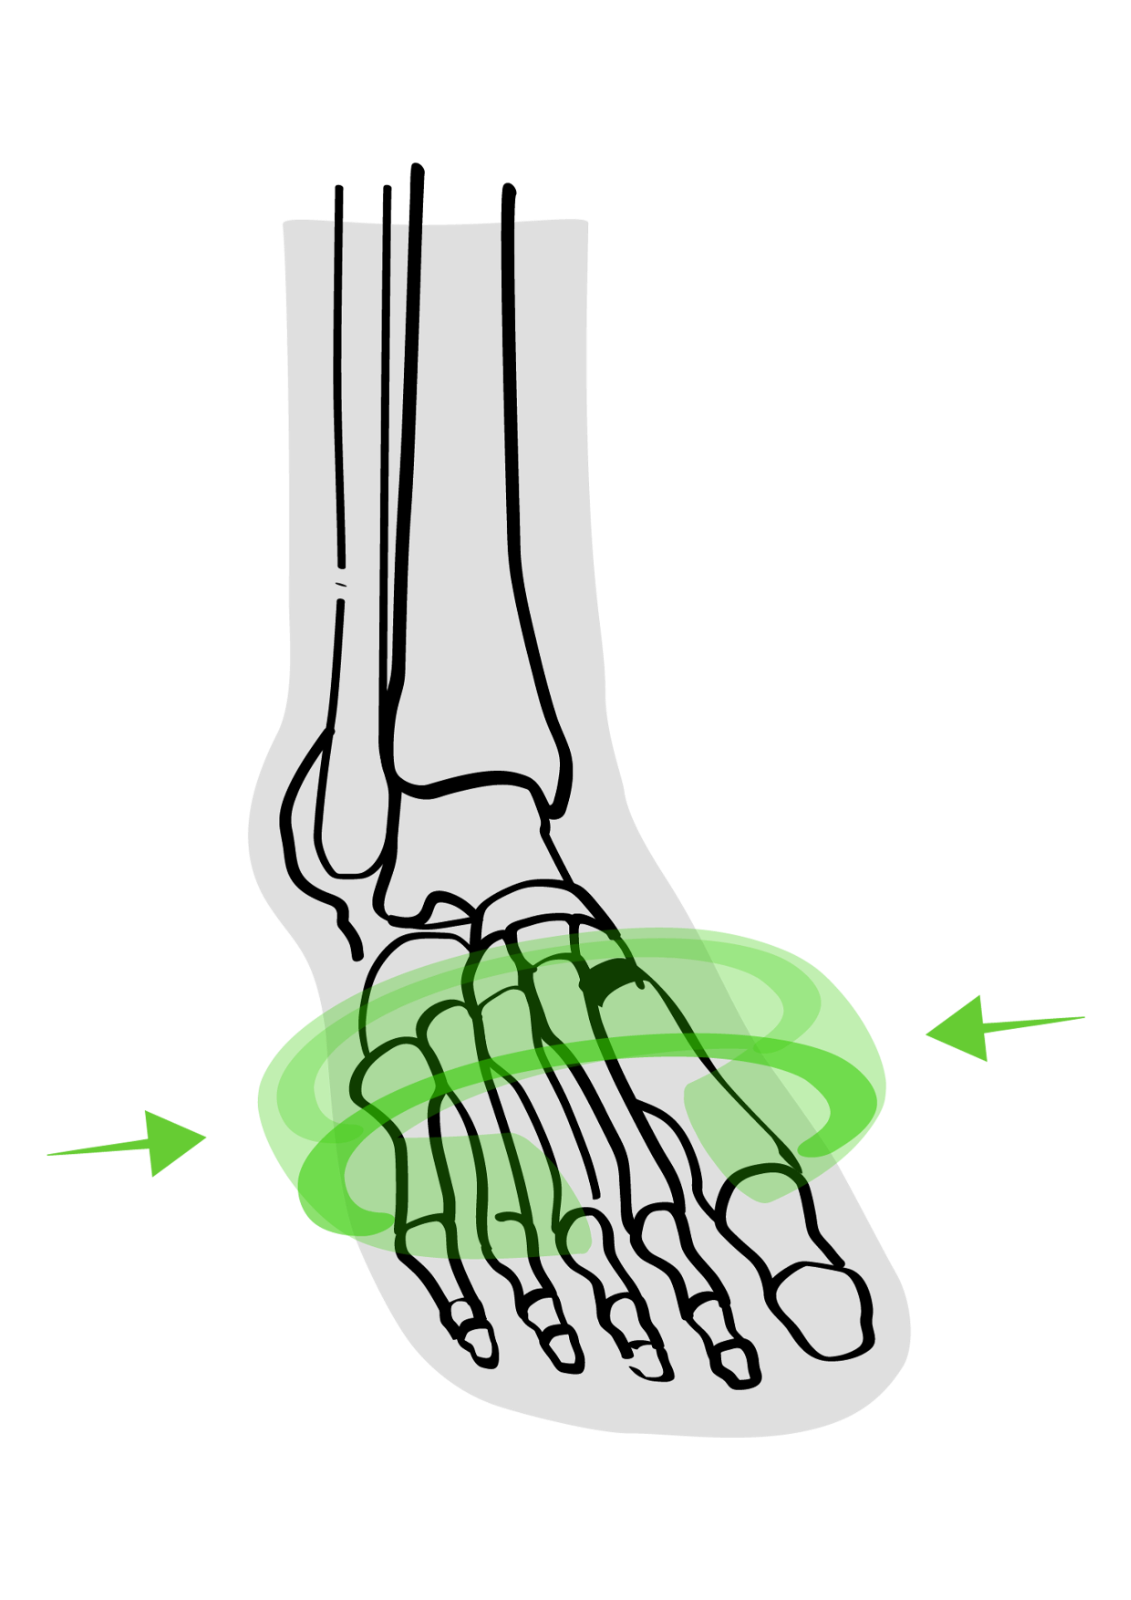

Splay Foot is challenging to live with, to say the least! The condition can affect one or both feet and often leads to various issues and symptoms that can interfere with daily activity and quality of life.

Those who suffer from Splay Foot will notice a reduction in their quality of life due to the pain and discomfort caused. If not treated, the whole body can become impaired due to the wrongly positioned placement of the foot.